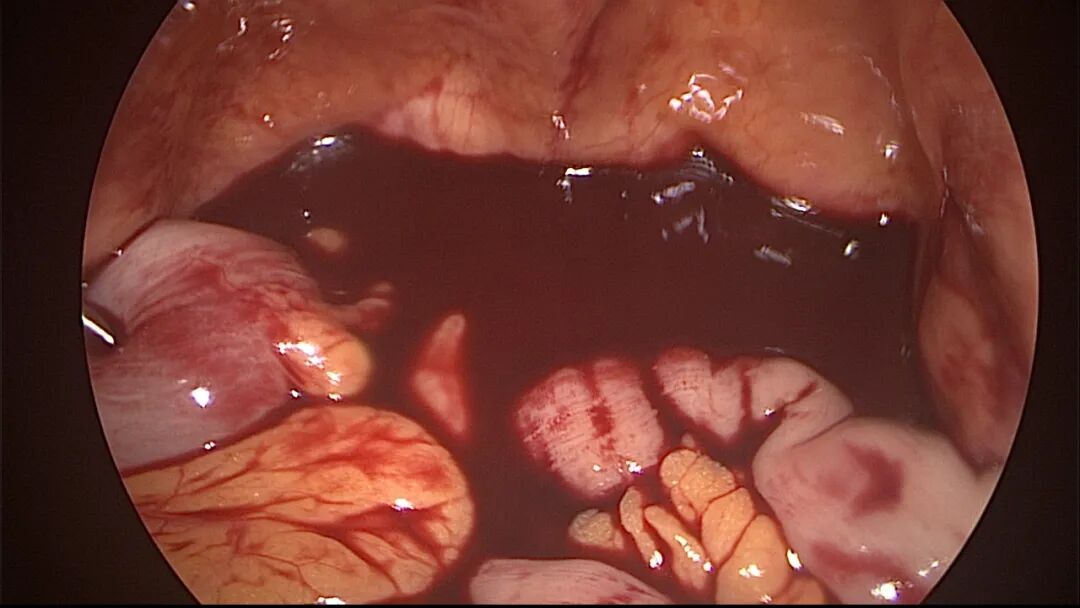

外院取环失败,子宫从切口憩室处穿孔

宫腔操作假道发生率较高,穿孔发生率较低,假道和穿孔原因一致,力度大了就穿孔了。假道或穿孔大多发生在门诊取环、人流、清宫等病例,尤其是绝经后取环占比最多。子宫位置特殊、宫颈管狭窄,探针探查、扩宫或取环钩操作时形成假道或穿孔,立即停止操作,经评估后做宫腔镜处理。宫腔操作动作要轻柔,注意子宫收缩节律,不要在子宫收缩时突然进入宫腔。穿孔可能损伤宫底或宫腔前后壁血管,缓慢持续出血导致盆腔积血。穿孔后是否探查盆腔、修补子宫需详细评估病情:血常规、B超、腹部刺激症状、失血体征、后穹隆穿刺等,大多数穿孔不需要手术探查。宫腔镜术中出现难以控制的出血大多发生于靠近子宫动静脉的粘膜下肌瘤、侧壁宫腔粘连、胚物残留合并动静脉瘘及子宫纵膈手术等,直视下电凝止血是最佳办法,球囊压迫止血影响因素太多,包括出血部位、动静脉区别、血管大小、子宫收缩情况、球囊大小、牵拉球囊力度等,效果一言难尽,尽量不采用。腹腔镜下缝合子宫壁、经阴道宫颈侧壁缝合(都不一定能缝到出血血管)、艾丽斯钳钳夹宫颈等方法可压迫止血或明显减少出血。手术越熟练、缩短手术时间、快速完成手术,手术越安全,避免严重水中毒发生。甘露醇或5%葡萄糖膨宫,手术每隔20~30分钟,建议速尿(半衰期为30~60分钟)半支静推;生理盐水膨宫,手术时间持续30~45分钟,速尿半支静推,总时间最好控制在60分钟以内,不要超过90分钟,必要时分次手术。速尿具体使用量及间隔时间根据膨宫介质、膨宫压力、手术难易及时间长短、创面及血管暴露情况、病人生命体征、麻醉情况等决定。